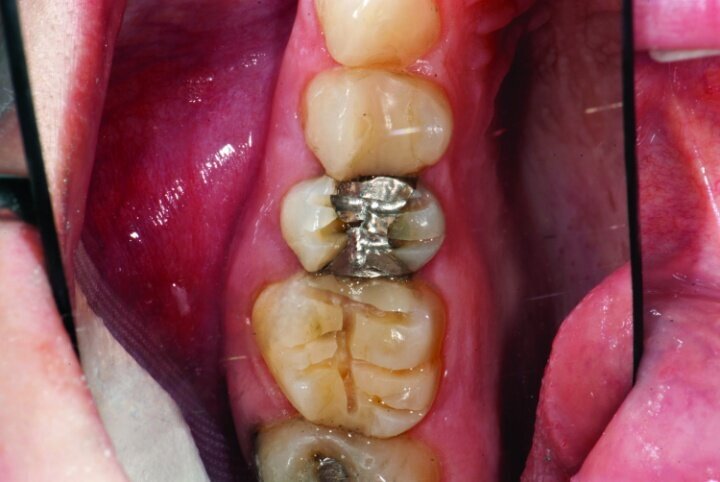

The final result was minimally invasive restorations that appear and function naturally, while decreasing risk of tooth fracture, and minimize further risk to the teeth. (Figs. 35a–36b).